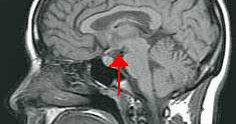

Health Rising: “ME/CFS Autopsy Study Finds a Wrecked HPA Axis: The 2025 IACFS/ME Conference Report #3” “.. they found almost no CRH producing neurons in the ME/CFS patients. That suggested that a general suppression of the hypothalamus…” https://t.co/FzLH1D1XK6

Tweet card summary image

healthrising.org

A Dutch ME/CFS autopsy report findings multiple severe problems in the HPA axis of ME/CFS patients.